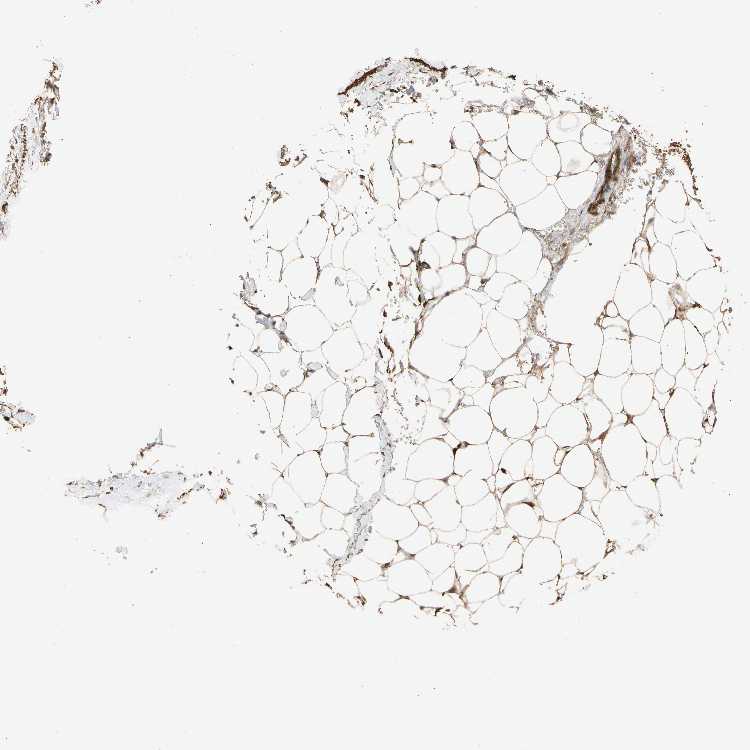

SOFT TISSUE 1 - Antibody stainingi

Antibody staining in the annotated cell types in the current human tissue is reported as not detected, low, medium, or high, based on conventional immunohistochemistry profiling in selected tissues. This score is based on the combination of the staining intensity and fraction of stained cells.

Each image is clickable and will lead to virtual microscopy that enables deeper exploration of all samples and also displays staining intensity scores, fraction scores and subcellular localization as well as patient and tissue information for each sample.

Antibody HPA007653

Fibroblasts High

Peripheral nerve High